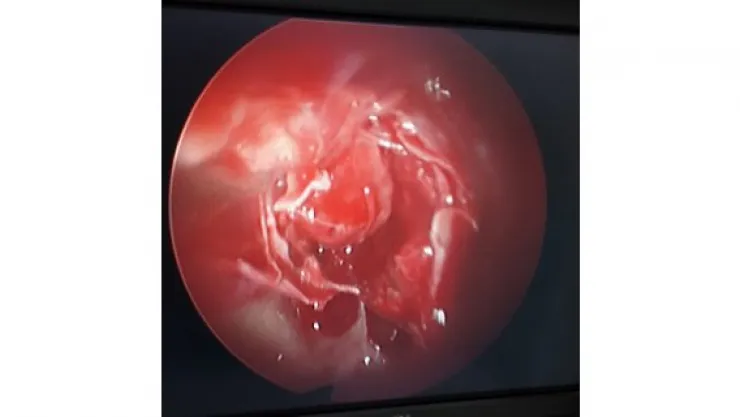

Beyin Cerrahisi Op. Dr. Hıdır Özer yaptığı açıklamada, bir hastanın baş dönmesi ve görmede azalma şikayeti ile kendilerine başvurduğunu, çekilen filmlerin sonucunda beyin tabanında hipofiz tümörü tespit edildiğini söyledi.

Yapılan açıklamada Ameliyat hipofiz bezini bulunduran sella bölgesine ulaşma aşaması KBB uzmanı Op. Dr. Erdem Özdemir tarafından gerçekleştirilirken bu aşamadan sonra hipofiz bezine ulaşılarak patolojinin çıkartılması Beyin Cerrahisi Uzmanı Op. Dr. Hıdır tarafından yapıldığı belirtildi.

“Ameliyat sonrası burun tamponu gerektirmemesi, hipofizi içinde barındıran anatomik yapının (sella), sadece düz görüş sağlayabilen mikroskoplarla görülmesi mümkün olmayan bölgelerinin açılı endoskoplar kullanılarak görülebilmesi sayesinde hastalığın tam olarak temizlenebilmesi, sfenoid sinüs yan duvarında yer alan şah damarı, görme siniri gibi kritik anatomik yapıların açılı endoskoplarla kolayca takip edilerek korunması ve hastanede kalış süresinin kısalması...”